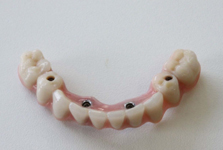

Bezzubá čelist je hlavní indikací pro ošetření pomocí implantátů. Zejména celkové zubní náhrady v dolní čelisti mají velice nízkou stabilitu a držení díky velkému úbytku kosti.

S pomocí zubních implantátů můžeme díky různým kotevním systémům (třmeny, kulové hlavy, Locatory) zajistit stabilitu a držení protézy nebo při použití většího počtu implantátů zhotovit pevné náhrady – můstky nalepené nebo našroubované na pevno na implantáty.

S těmito typy náhrad můžeme dosáhnout perfektní funkci, výbornou estetiku, fonetiku a současně zajistit u pacienta možnost dobré hygienickou péče a čištění, která je pro životnost implantátů velice důležitá.